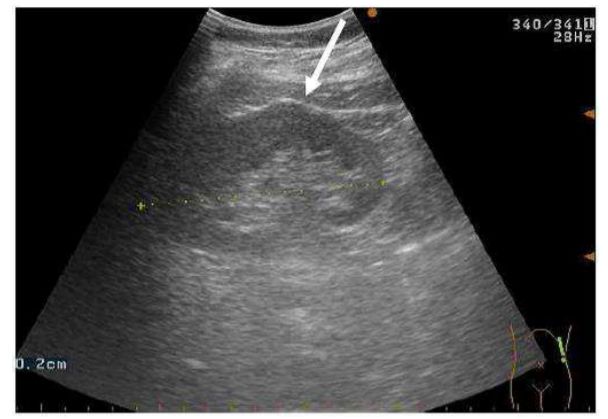

71.15歲女孩乳房超音波檢查呈現病灶如附圖,最有可能的診斷為下列何者? (A)良性纖維腺瘤 (B)良性囊腫 (C)惡性乳癌 (D)良性脂肪瘤